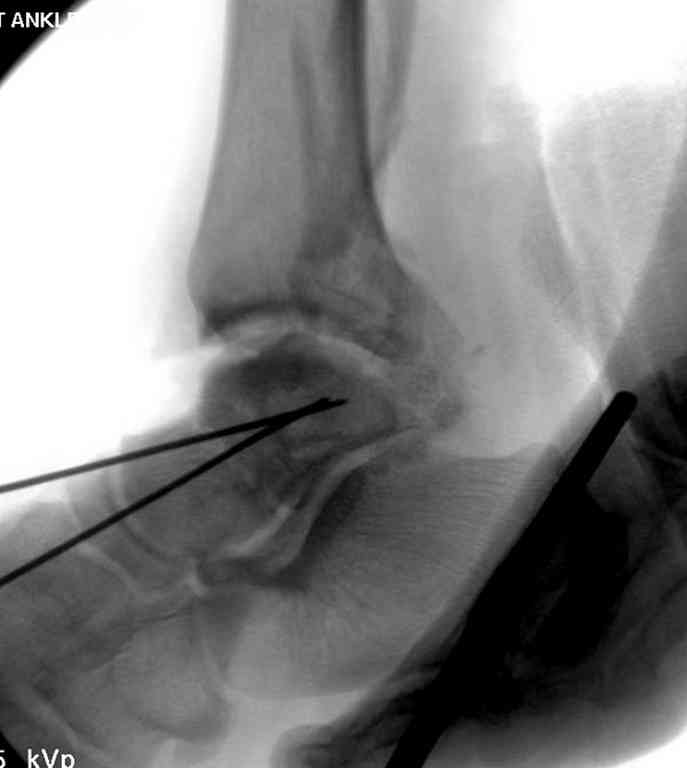

Второй случай прооперирован вчера.

10 дней назад поступил с открытым повреждением медиальной лодыжки и переломо вывихом таранной кости. Ургентно сделана репозиция с наложением наружного фиксатора + Irrigation&Debridment.

Вчера провели фиксацию.

Из-за многооскольчатости дистальной части малоберцовой, где невозможно было провести фиксацию шурупами, перелом зафиксирован подпирающей пластиной, которая должна служить дополнением отсутствующей дистальной части малоберцовой (lateral cortex substitute).

Для стабильности два шурупа на синдесмоз.